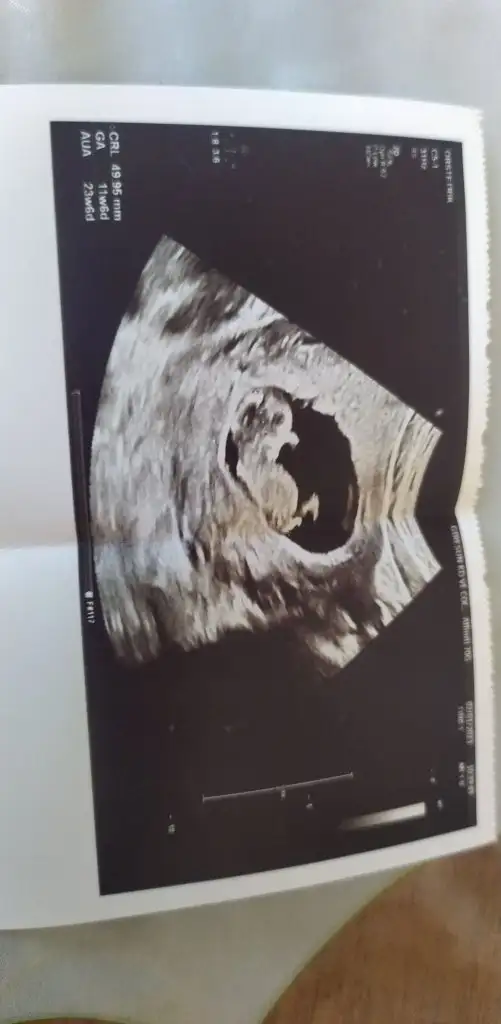

Bu 12 haftalık görüntüsü burda belli olmadı da 15 sinci haftadami belli oldu kafamı bu karıştırıyor

Evet bunda çok belli değil aslında ve hangi haftada göründüğü önemli değil görünmüş olması yeter ve bende kağıda tekrar baktım sen erken yatırmışsın tam 12+0 olmadan yapılmıyor doktorun hatası inşallah sağlıkla gelecek bebeğin ve bunların hepsi geçecek gazıyla uykusuyla uğraşacaksın 🤲🤲

Elini zaten burnunun üstüne koymuş nasıl gördük kemik olmadığını resmen eli üstünde anneler böle bizden çok panik oluyorlar haklılarda işte genede panik yapmadan başka doktora damı gitsen ki